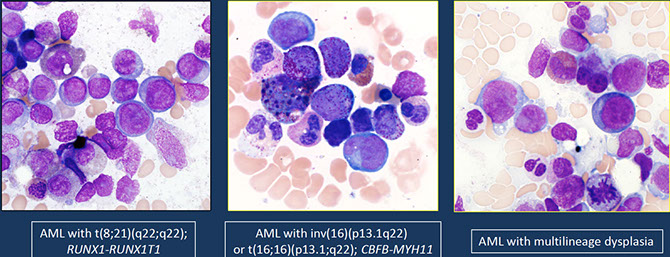

- Acute myeloid leukemia with t(8;21)(q22;q22.1); RUNX1-RUNX1T1

- Acute myeloid leukemia with inv(16)(p13.1q22) or t(16;16)(p13.1;q22); CBFB-MYH11

Acute myeloid leukemia with myelodysplasia-related changes